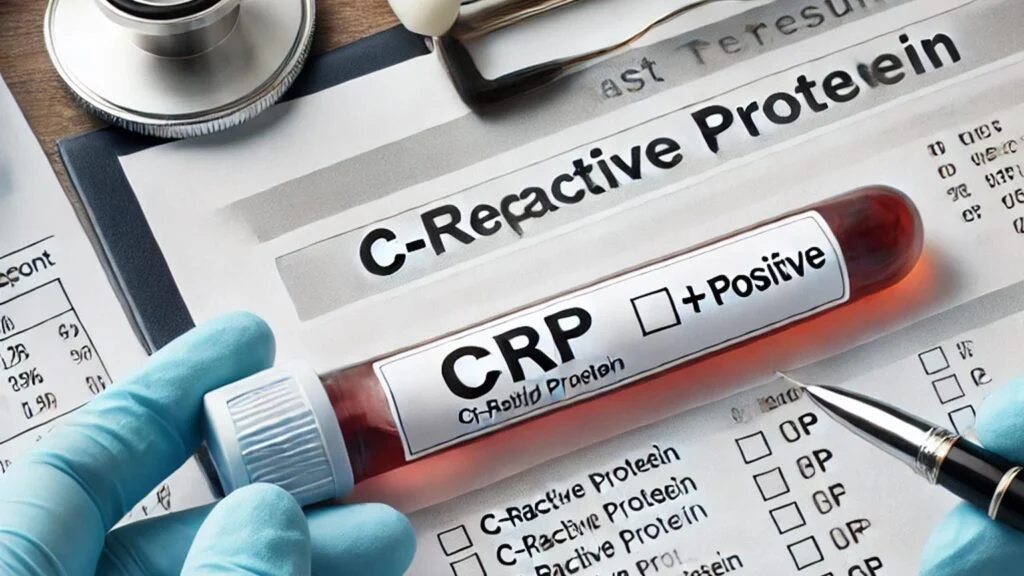

آیا CRP مثبت خطرناک است؟

آزمایش CRP یکی از آزمایشهای مهم برای بررسی سطح التهاب در بدن است. بسیاری از افراد هنگام دریافت نتیجه آزمایش خود با عبارت CRP مثبت مواجه میشوند و این سوال برایشان پیش…

آیا CRP مثبت خطرناک است؟

آزمایش CRP یکی از آزمایشهای مهم برای بررسی سطح التهاب در بدن است. بسیاری از افراد هنگام دریافت نتیجه آزمایش خود با عبارت CRP مثبت مواجه میشوند و این سوال برایشان پیش میآید که آیا CRP مثبت خطرناک است؟ سطح بالای CRP میتواند…